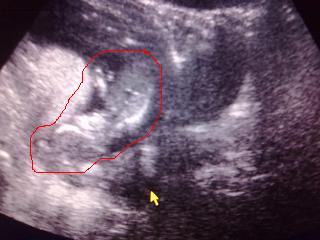

Dike bekarikáztam neked a Babát! Jah és az is lehet, hogy azért látszik "csak" ennyire, mert hájas vagyok :(

mona: nemhiszem, hogy a "háj" befolyásolná ezt. csak rosszul feküdt :) de így hogy mutatod mit kell nézni,már látom nagyjából :D